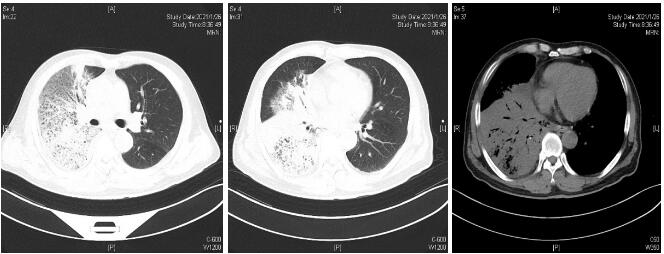

患者经过近1周治疗,临床症状较前好转,心衰纠正,炎症指标明显下降,于1月31日体温正常后转普通病房。感染方面美平降级为头孢派酮舒巴坦,继续多西环素治疗。2月2日外送标本DNA测序鉴定为Balneatrix alpica,即阿尔卑斯浴者菌。后续患者出现胸膜炎性胸痛,间断气促,复查肺部CT提示右侧胸腔积液量增多,给予穿刺引流,胸水外送经DNA鉴定报高山巴氏发菌,即Balneatrix alpica,至此患者感染的病原菌明确,考虑此菌为少见菌,对抗菌药物敏感性较高,后续抗生素方案降解为左氧氟沙星500 mg/d,经治疗3周后患者出院,后期随访追踪无不适。

| 图 3 2月22日出院胸部CT平扫 |